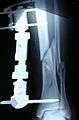

The following case study illustrates the Ilizarov apparatus treatment procedure for a fractured limb. The photographs are of the same patient during the course of treatment.

X-Ray of the fracture site (three months following fracture). Note formation of bone callus around fracture site.

X-Ray of the fracture site, part 2 (three months following fracture). Note formation of bone callus around fracture site.

X-Ray of the fracture site, part 2 (four months following fracture)